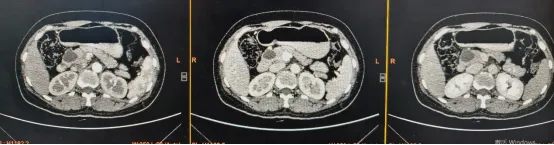

李晓勇教授、陈艳军主任通过影像学技术仔细评估肿瘤范围及位置后,明确表示:可以施行DPPHR术式——切除胰头部肿瘤,同时尽可能保留十二指肠等器官功能完整。

640_副本

面对患者5cm的胰头占位,病变体积大、与周边组织粘连紧密,手术操作空间极小。稍有不慎,就可能损伤血管、胆管或十二指肠,引发大出血、胆瘘、肠瘘等严重并发症。

术前,李晓勇教授、陈艳军主任团队通过多学科联合会诊(MDT),结合影像学检查,精准制定手术方案,明确病变边界与血管走行。

术中,专家团队凭借精准操作,仔细分离病变与周边正常组织,全程悉心保护十二指肠的血供与神经支配,严格守护Oddi括约肌的完整性。